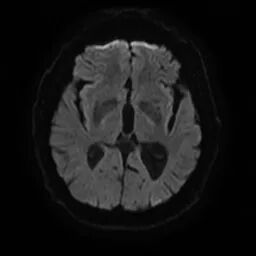

颅脑磁共振+头颈MRA:未见新发梗死;右侧颈内动脉C1段重度狭窄。